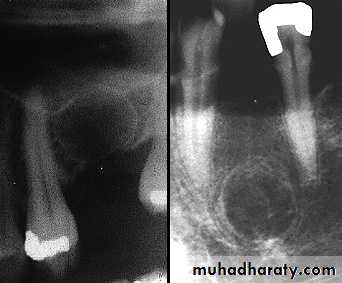

Residual Cyst

Residual and lateral radicular cyst

Lateral radicular cysts can occasionally form at the side of non vital tooth as a result of the opening of a lateral branch of the root canal.They are rare and must be distinguished from lateral periodontal cysts which are another pathological entity.